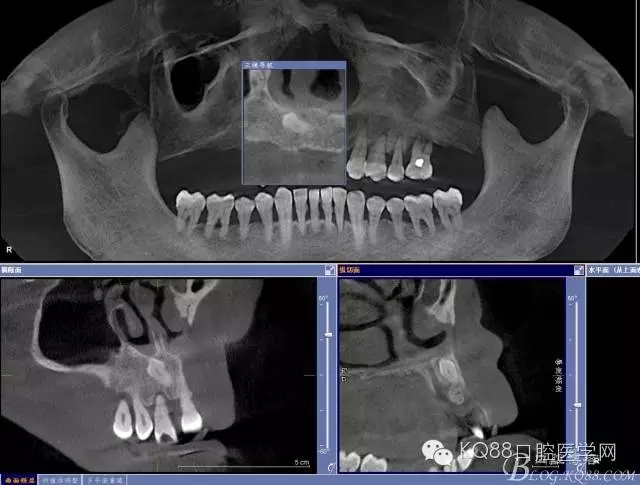

輔助檢查:ct示骨密度良好,11 12區(qū)域骨下有一水平向埋伏牙,15 16區(qū)域骨高度2.5-3mm,骨寬度6-9mm。